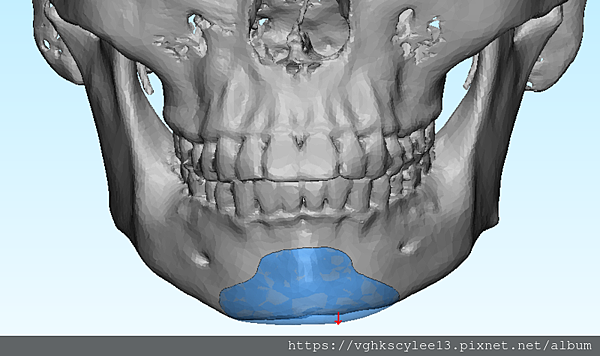

(下圖)3D模擬後工程師版的設計下巴假體的外型。

經過李醫師醫師對客戶外型的判斷,修改工程師的設計,建議更改後的假體模型(下圖)

(上圖)經過李醫師醫師對客戶外型的判斷,修改工程師的設計,建議更改後的假體模型。所以嘍,醫師的美感與專業度必須要做判斷,3D列印只是精準工具但是必須有專業醫師的判斷才可以完美!

下圖: 在李醫師確認後完美精準例印

窄小後縮的下巴,以精準3D列印技術來客製化醫師判斷後的外型下巴假體,一起改善嘴形相對的狀態。

窄小後縮的下巴,以精準3D列印技術來客製化醫師判斷後的外型下巴假體,一起改善嘴形相對的狀態。

3D模擬後 列印出吻合的設計下巴假體

下圖:或是以3D列印導板客製化下巴假體,以goretex材料按下巴導板來雕刻適合的形狀來訂製下巴,必要時把不規則的或不對稱骨頭磨平來改變術前傾斜。

下圖:後縮小下巴會堆積雙下巴和嘴邊肉皮膚,視覺老態。經過客製化3D導航下巴改善外觀老態,提升年輕化。

(下圖)高度客製化的goretex雕刻下巴假體,改善嘴邊肉的支撐。

下圖:3D列印導航 客製化goretex假體